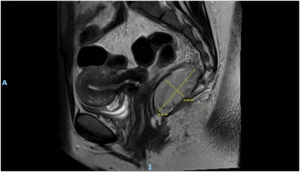

Imaging via MRI and CT demonstrated a complex, encapsulated lesion with peripheral enhancement and restricted diffusion. Multidisciplinary evaluation suggested a congenital epidermoid or duplication cyst. Given the absence of malignancy and surgical complexity, a conservative management strategy was adopted.

Figure 1: Figure 1 Duplication cyst 2025 MRI sagittal plane

Figure 2: Figure 2 Duplication cyst 2025 MRI sagittal plane